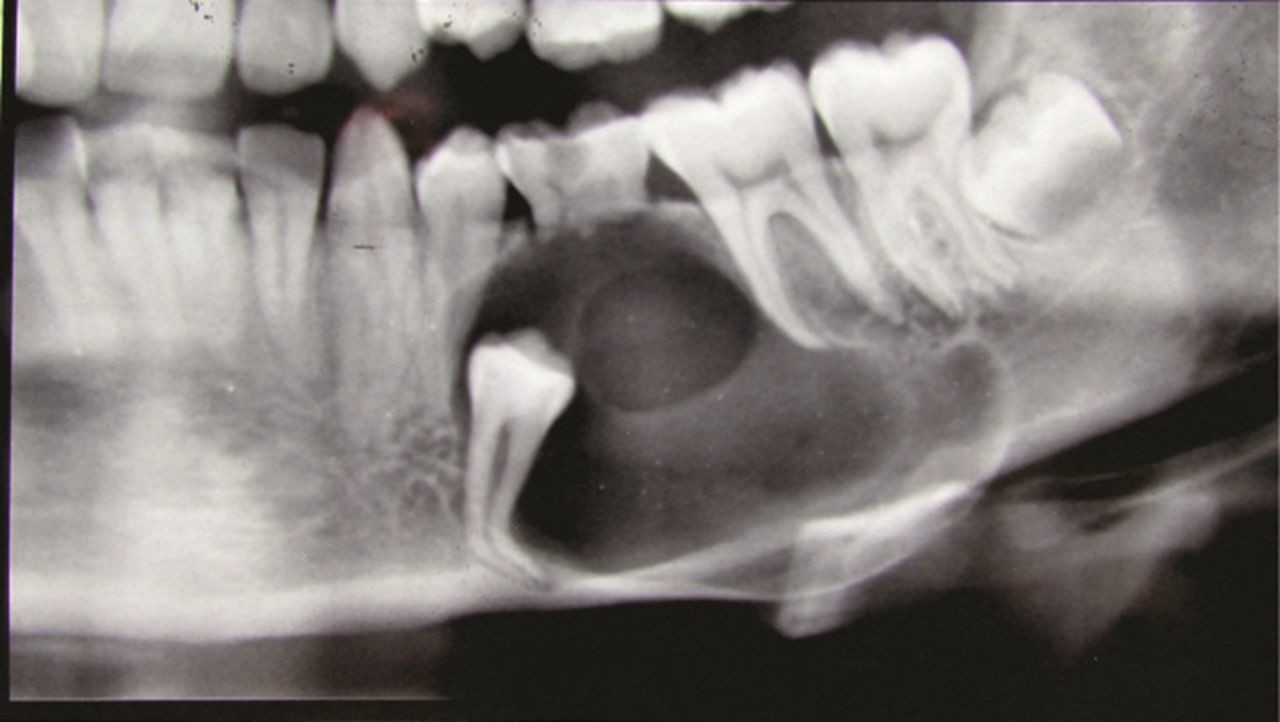

What is a dentigerous cyst?

Dentigerous cysts are the second most common type of odontogenic cyst, which is a fluid-filled sac that develops in the jaw bone and soft tissue. They form over the top of an unerupted tooth, or partially erupted tooth, usually one of your molars or canines. While dentigerous cysts are benign, they can lead to complications, such as infection, if left untreated.

What causes it?

Dentigerous cysts are caused by a buildup of fluid over the top of an unerupted tooth. The exact cause of this buildup is unknown.

How is it diagnosed?

Small dentigerous cysts often go unnoticed until you have a dental X-ray. If your dentist notices an unusual spot on your dental X-ray, they may use a CT scan or MRI scan to make sure it’s not another type of cyst, such as a periapical cyst or an aneurysmal bone cyst.

In some cases, including when the cyst is larger, your dentist may be able to diagnose a dentigerous cyst just by looking at it.

How is it treated?

Treating a dentigerous cyst depends on its size. If it’s small, your dentist might be able to surgically remove it along with the affected tooth. In other cases, they might use a technique called marsupialization.

Marsupialization involves cutting open the cyst so it can drain. Once the fluid has drained, stitches are added to the edges of the incision to keep it open, which prevents another cyst from growing there.

What are the complications?

Even if your dentigerous cyst is small and not causing any symptoms, it’s important to have it removed to avoid complications. An untreated dentigerous cyst can eventually cause:

infection

tooth loss

jaw fracture

ameloblastoma, a type of benign jaw tumor.

Living with a dentigerous cyst

While dentigerous cysts are usually harmless, they can lead to several problems if left untreated. Talk to your dentist about any swelling, pain, or unusual bumps in your mouth, especially around your molars and canines. In most cases, dentigerous cysts are easy to treat, either through excision or marsupialization.